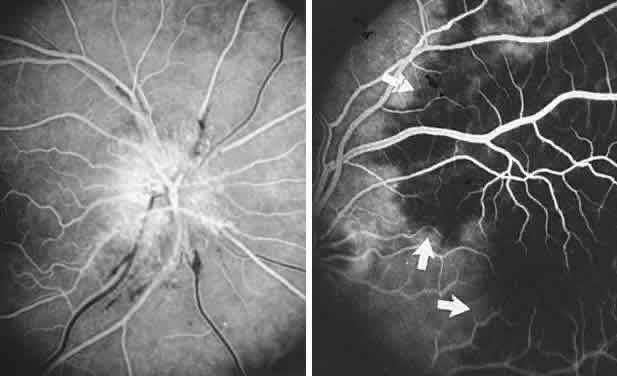

The onset of retinal arterial occlusion rarely goes unnoticed by the patient, but unlike venous thrombosis, arterial occlusions of a minor degree may be difficult to discern ophthalmoscopically, especially if days or weeks pass before the fundus is examined. Muci-Mendoza et al42 used fluorescein fundus angiography to demonstrate ophthalmoscopically occult emboli and post-embolic endothelial damage after episodes of amaurosis fugax (see below, Carotid Atheromatous Disease).

With acute infarction, the retina becomes opaque and takes on a creamy or gray appearance. Atheromatous material in the form of “bright plaques” of cholesterol or other microemboli may be seen, especially lodged at arterial bifurcations (Fig. 5). Segmental arteriolar mural opacification (see Fig. 5D) may follow retinal microembolization by weeks to months, and such sheathing may be as useful as the recognition of the cholesterol embolus itself.43 ERG may show diminished B-wave amplitude, a finding indicating inner retinal ischemia. Weeks following retinal infarction, the optic disc becomes pale, and the arterial tree becomes narrowed in the sector corresponding to the arterial occlusion.

Fig. 5. Retinal microembolic phenomena. A. Bright cholesterol plaque (arrow) impacted at an arterial bifurcation. Thin crystal does not obstruct flow. B. Cholesterol crystals in disc vessels (arrows). Often, the plaque appears larger than the vessel diameter. C. Infarcted opaque retina. The artery contains emboli (? fibrin platelets) that have obstructed flow. D. Reactive opacification of the arterial wall. Fluorescein angiography demonstrated flow through this formerly occluded vessel.